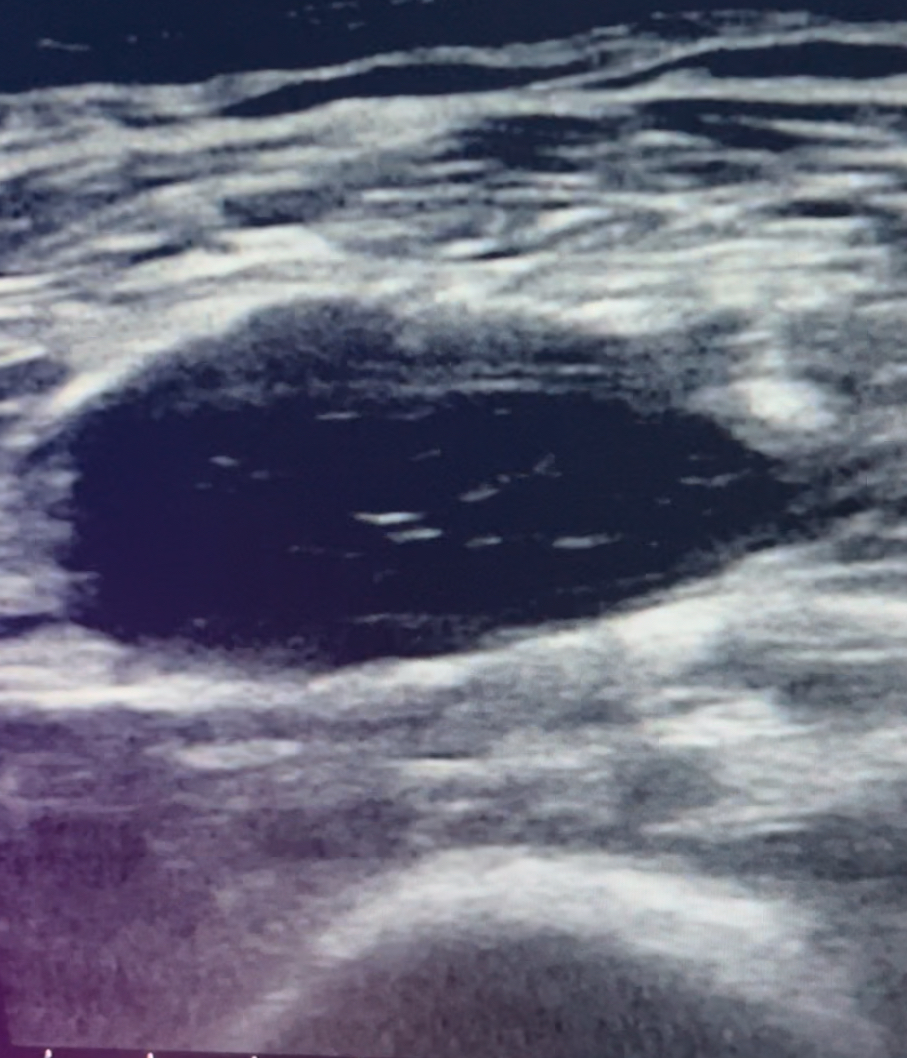

Ecografía: Contenido hipoecoico en espesor de músculo cuádriceps, compatible con rotura fibrilar.

Juicio clínico: Hematoma y rotura fibrilar.